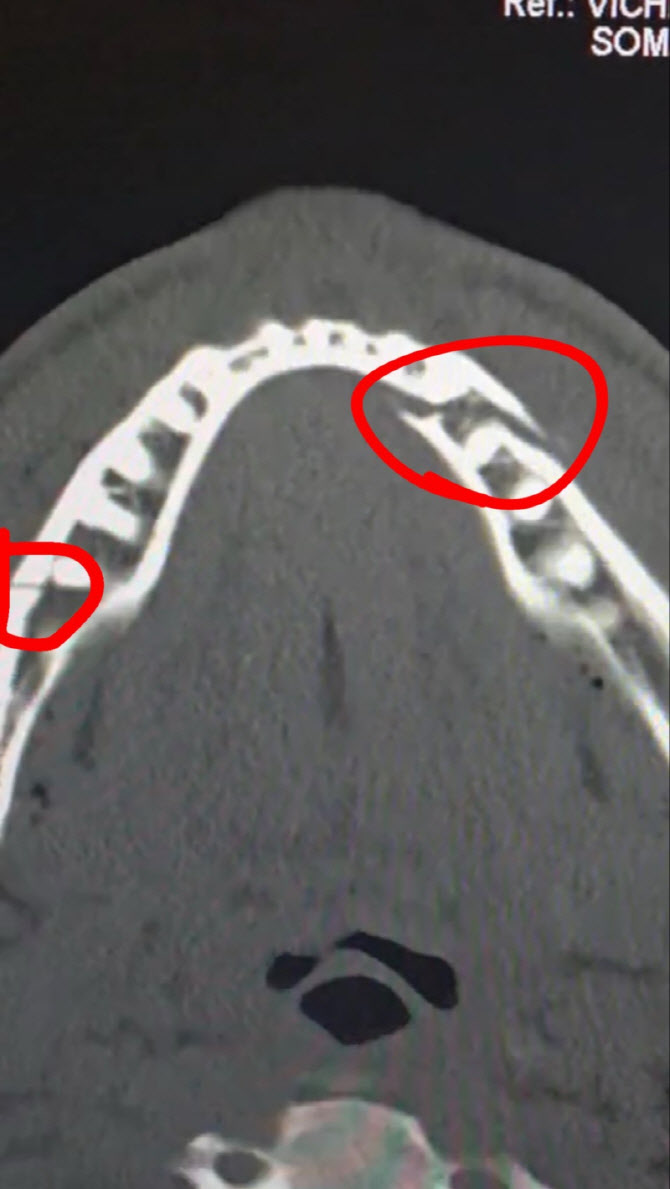

폴은 전 챔피언의 매서운 주먹맛을 제대로 느꼈다. 그는 “역대 최고 선수 중 한 명에게 제대로 한 방 먹었다”라며 “확실히 턱이 부러진 거 같다”고 말했다. 이후 병원을 향한 그는 사회관계망서비스(SNS)에 어금니 여러 개가 뒤로 밀린 엑스레이 사진을 올리기도 했다.

제이크 폴의 턱 엑스레이. 사진=제이크 폴 SNS

조슈아와 경기를 마친 폴은 잠시 숨을 고른 뒤 다시 링에 설 예정이다. 그는 “6년 동안 열심히 해왔으나 잠시 쉬어야겠다”며 “부러진 턱을 치료하고 제 체급 선수들과 싸우면서 세계 타이틀에 도전하겠다”고 말했다.